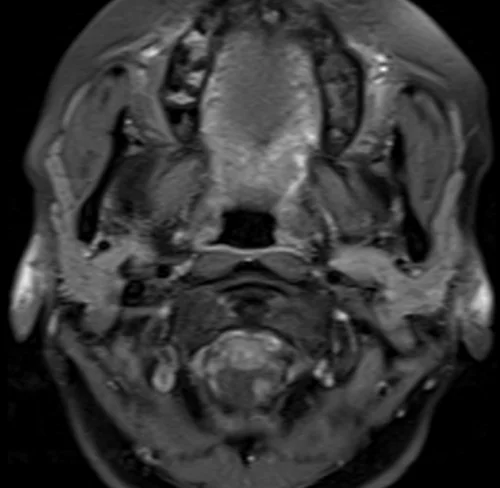

Neck MRA axial T1 fat sat images